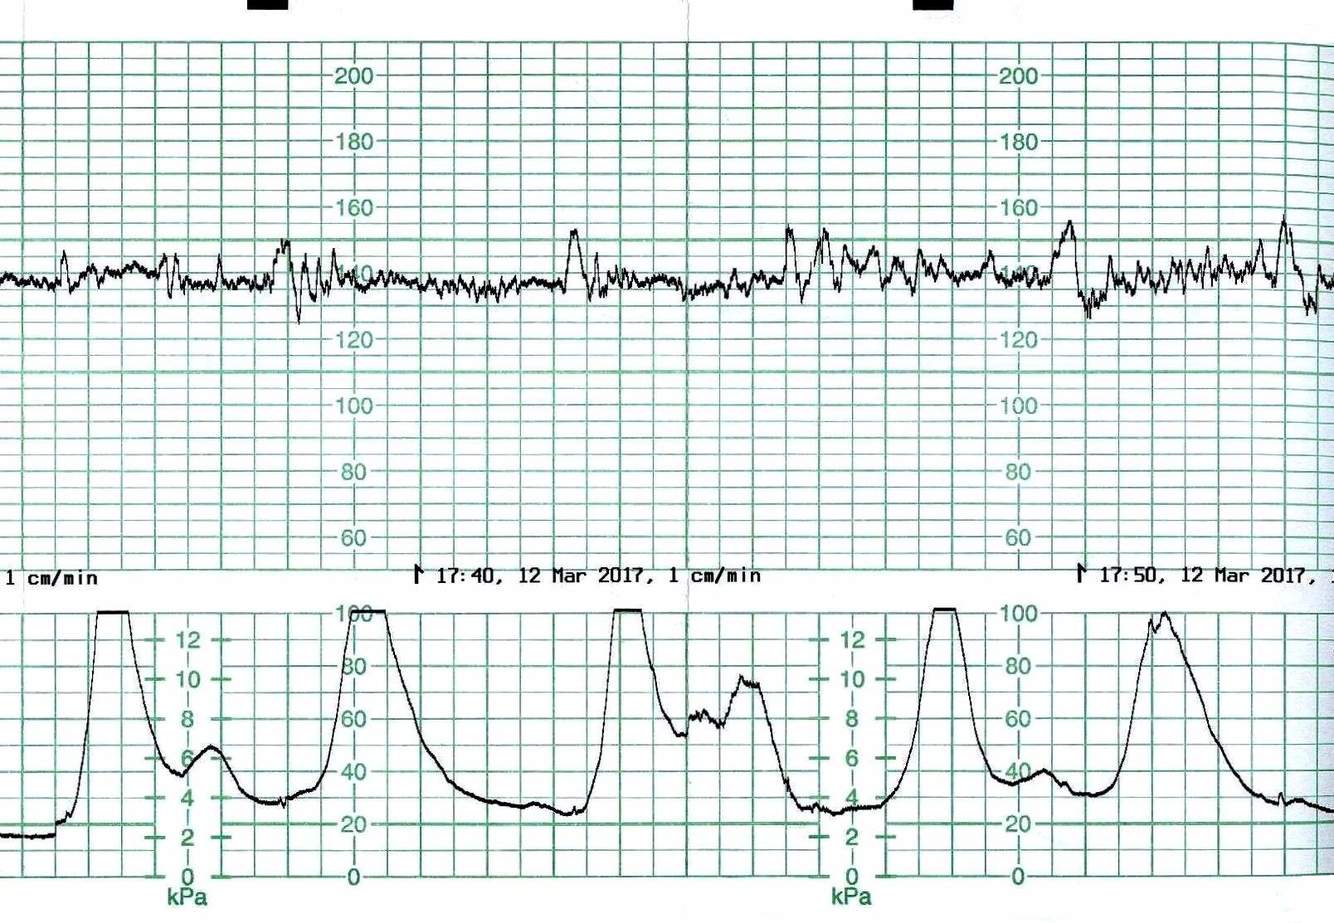

What does this CTG show?

Uterine Hyperstimulation. 5+ contractions in a 10minute period. Fetus is showing prolonged decelerations and bradycardia.

A acutely hypoxic fetus. Tachycardic with prolonged and late decelerations. With absent baseline variability.